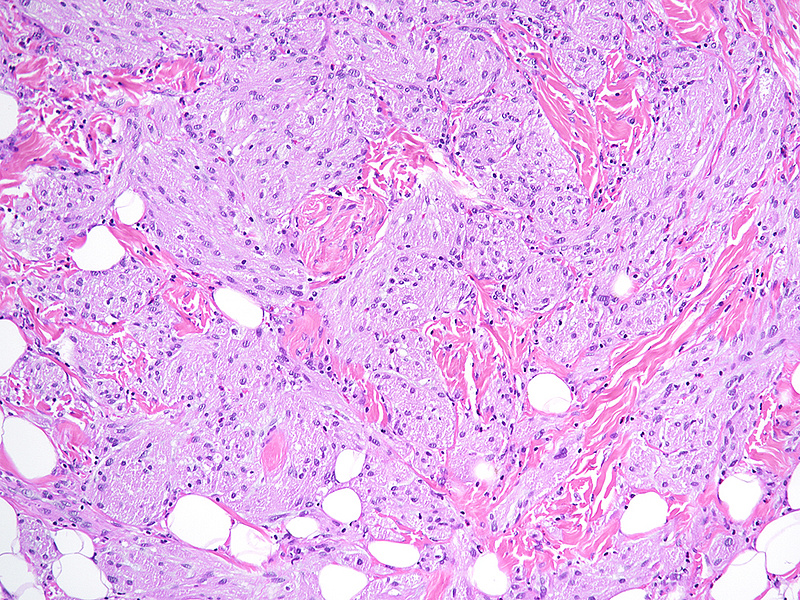

Histologically, we saw a submucosal proliferation of solid nests and ribbons of round to polyhedral cells, measuring approximately 6 mm in largest diameter (Panels A-B). The neoplastic cells generally contained small, uniform nuclei with inconspicuous nucleoli and abundant granular eosinophilic cytoplasm. They were separated by fibrous septa, which contained few inflammatory cells, mostly lymphocytes and few eosinophils (Panel C). In some areas, the neoplastic cells demonstrated cell spindling, still keeping the cytoplasmic features described above (Panel D). The lesion was ill-defined at the base, showing an infiltrative pattern into the surrounding adipose tissue within the submucosal layer (Panels E-F). The neoplastic cells were positive for PAS and strongly immunoreactive for S100-protein (Panels G-H), yet negative for keratin, CD117, DOG-1, and muscle markers, prompting final diagnosis of colonic granular cell tumour.

Granular cell tumors are common lesions in subcutaneous tissue. Gastrointestinal pathologists may encounter this form of peripheral nerve sheath tumour mainly in the oesophagus. In the colorectum, granular cell tumours prevail on the right side (coecum, around the ileocoecal valve, and within the ascending colon). On low power they are either infiltrative or well-defined, involving either the mucosa, submucosa (most common), or both. The cells are characteristically positive for PAS and S100-protein, but may also show positivity for SOX-10, NSE, and synaptophysin.